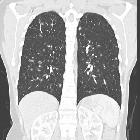

Pulmonary Langerhans cell histiocytosis has variable appearance depending on the stage of the disease, ranging from small peribronchiolar nodular opacities to multiple irregularly-shaped cysts. There is a mid and upper zone predilection .

As is usually the case, CT and especially HRCT is superior to plain chest radiography in identifying both the reticulonodular opacities and cysts . Distribution is the key in differentiating pulmonary Langerhans cell histiocytosis from other cystic lung diseases with a predilection for the mid and upper zones and regional sparing of the costophrenic recesses, anterior right middle lobe and lingula left upper lobe .

- cysts

- more pronounced later in the disease

- usually less than 10 mm in diameter

- may measure up to 2-3 centimeters in size

- the extreme bases may be preserved

- usually thin-walled, but on occasion may be up to a few millimeters thick

- confluence of 2 or more cysts results in bizarre shapes